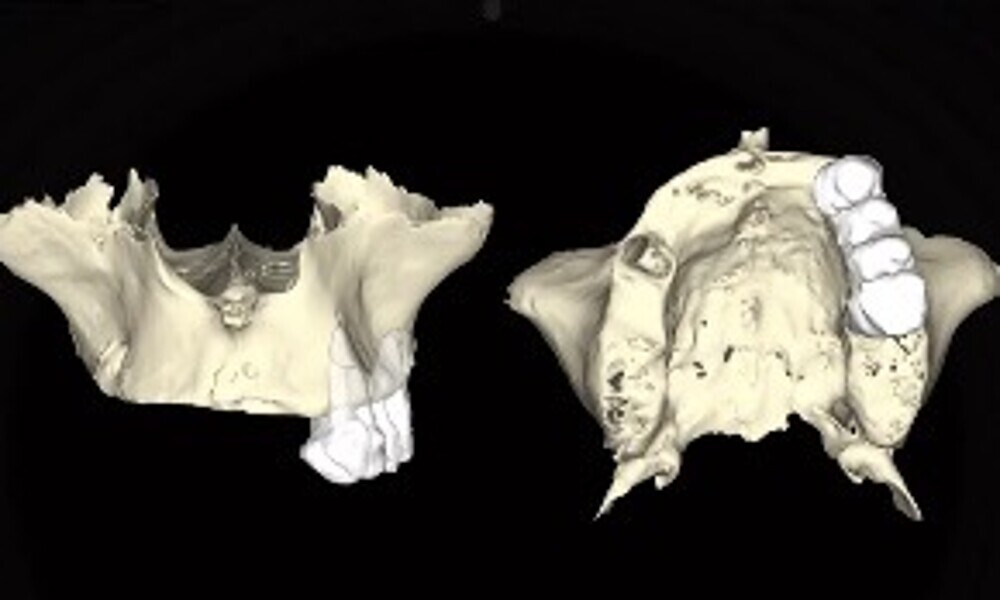

Extra-oral examination showed no significant abnormalities. The patient presented with a medium smile line (Figs. 1–3). The intra-oral examination revealed a fixed bridge spanning teeth #23–26 to which the removable metal partial denture attached (Fig. 4). Teeth #22–17 had been extracted a long time before, and the ridge in this region had healed. No plaque or inflammation was observed. The teeth exhibited mild to moderate attachment loss, but no endodontic or periodontic lesions or root fractures were observed (Figs. 5–8). Analysis of the panoramic radiograph indicated sufficient vertical and horizontal bone availability and adequate bone quality; therefore, there was no need for guided bone regeneration (Fig. 9). According to the International Team for Implantology’s SAC classification, the case was categorised as advanced to complex.

For the procedure, we decided on the Straumann Pro Arch approach, involving the immediate placement of six Straumann BLX implants (Roxolid material and SLActive surface) in the upper jaw. This digitalised method would be performed after atraumatic extractions, and a provisional prosthesis was planned to be placed on the same day.

2. digital planning using coDiagnostiX (Dental Wings; 13–15);

The fit of the previously sterilised provisional guide and surgical guide was then verified (Figs. 21 & 22). The surgical guide was positioned, aligning it with the arch and extraction sockets. Subsequently, the holes for the anchor pins were drilled and the pins inserted (Figs. 23 & 24). The surgery was initiated using a mucosa punch at 15 rpm through the sleeves of the surgical guide. This method allowed for blade-free incision with minimal trauma (Figs. 25 & 26). After removing the mucosal punch, the surgical guide was reinserted to begin the placement of the implants (Fig. 27). The surgical protocol, provided alongside the surgical guide, recommended the sequence of instruments required to prepare each implant site. The osteotomy sites were prepared following the manufacturer’s recommended drilling protocol using a copious amount of saline irrigation, and the implants placed as follows and parallelism checked (Figs. 28–31):